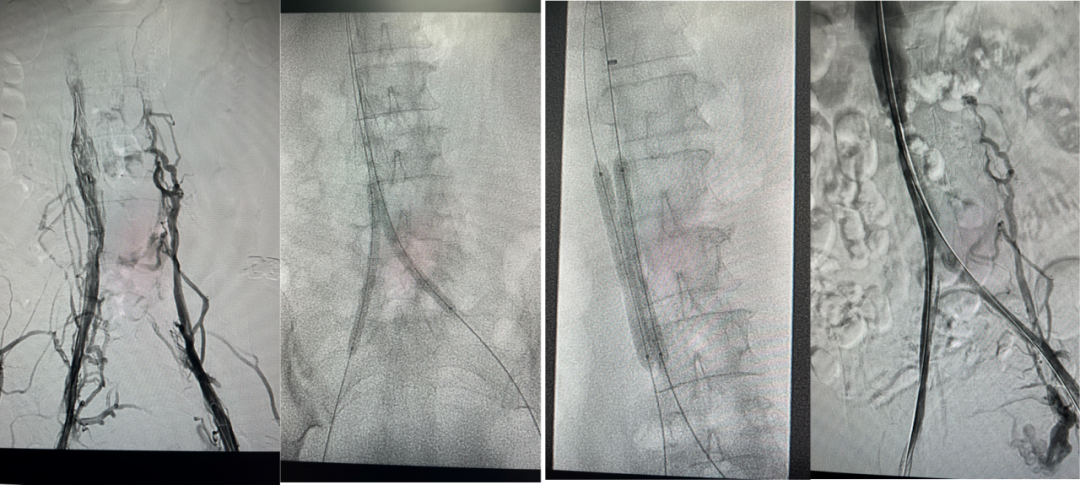

图:AngioJet +手动抽吸血栓

图:抽吸后双髂静脉及下腔静脉复通+滤器置换

图:足量抗凝两周后回收临时滤器

图:2年后随访结果

图:第一次:扩张下腔静脉、髂静脉并取出滤器2025.2.13

图:二次复查CT并进行球囊扩张2025.3.31